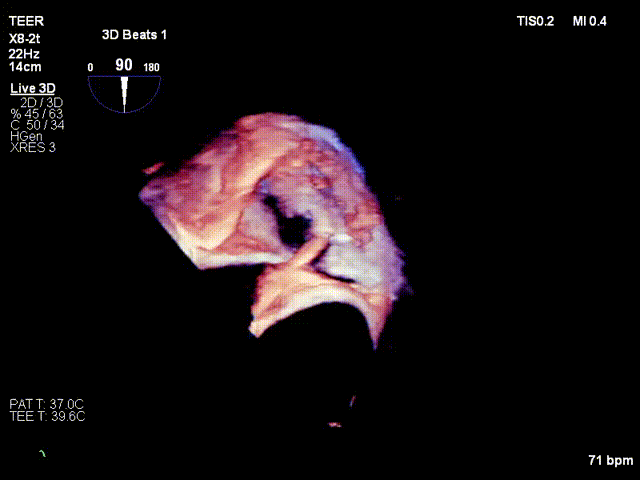

Efficacy evaluation after implantation of the first clip

Implanting the second clip at the anteroposterior commissure following the same procedure